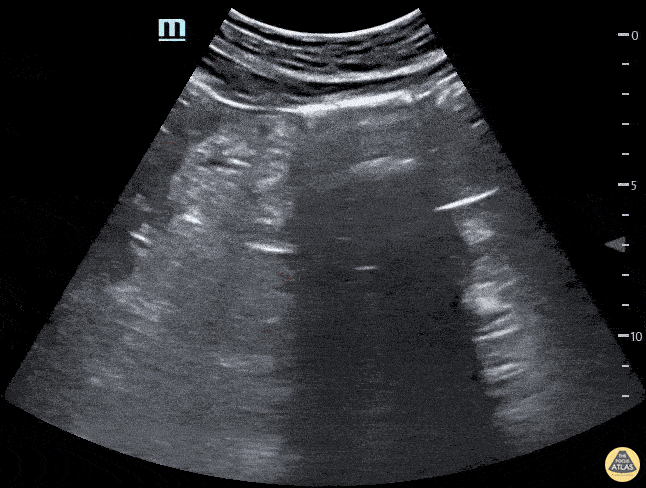

Renal/GU - Horseshoe Kidney Longitudinal

Horseshoe kidney. No kidney was identified in either flank area, this anterior abdominal view shows one large kidney that is anterior to the Aorta. Marion Memmott, DO; Michael Bernard, DO; Central Michigan University Emergency Medicine Residency